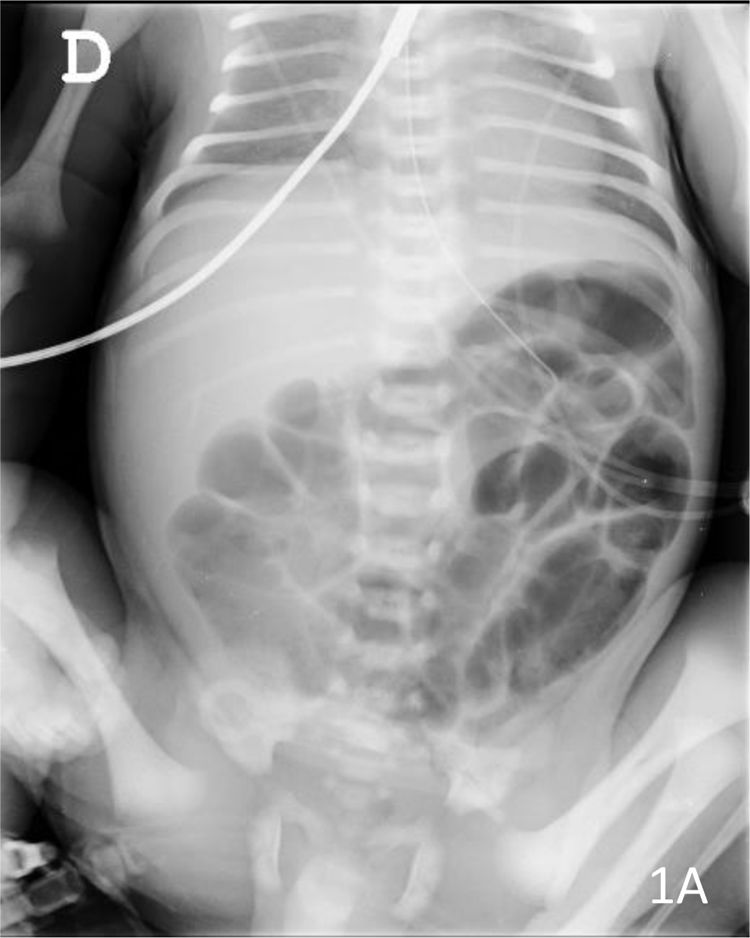

En neonatos, la obstrucción intestinal puede ser diagnosticada mediante una serie de hallazgos radiológicos característicos. La evaluación radiológica es crucial para diferenciar entre las diversas causas de obstrucción intestinal, que pueden ser de origen alto o bajo, y para determinar el manejo adecuado.

1. Radiografía Abdominal: Es la primera línea de imagen utilizada para evaluar la obstrucción intestinal en neonatos. Los hallazgos típicos incluyen dilatación de asas intestinales y la presencia o ausencia de niveles hidroaéreos, lo cual puede indicar si la obstrucción es proximal o distal. Por ejemplo, la «burbuja única» se asocia con atresia esofágica, la «doble burbuja» con atresia duodenal, y la «triple burbuja» con atresia yeyunal.[1-2]

Los hallazgos ecográficos de íleo paralítico en neonatos pueden incluir varios signos característicos. Según la literatura médica, el íleo paralítico se manifiesta por la dilatación de los intestinos, tanto del intestino delgado como del grueso, sin evidencia de obstrucción mecánica.[1] En el contexto de neonatos, especialmente aquellos con encefalopatía hipóxico-isquémica, se ha observado una disminución o ausencia de peristalsis, lo cual es un indicador clave de íleo paralítico.[2] Además, puede haber un aumento de la ecogenicidad de la pared intestinal y la presencia de líquido libre en la cavidad abdominal.[2] Estos hallazgos son consistentes con la falta de movimiento intestinal y la acumulación de contenido intestinal debido a la parálisis del músculo liso intestinal.

Es importante diferenciar el íleo paralítico de la obstrucción mecánica, ya que los hallazgos ecográficos pueden ser similares, pero la ausencia de peristalsis y la dilatación generalizada sin un punto de obstrucción son más indicativos de íleo paralítico.[1] La ecografía puede ser particularmente útil en la evaluación temprana, ya que permite identificar cambios en la peristalsis y la estructura de la pared intestinal antes de que se desarrollen signos radiográficos más clásicos.[1]